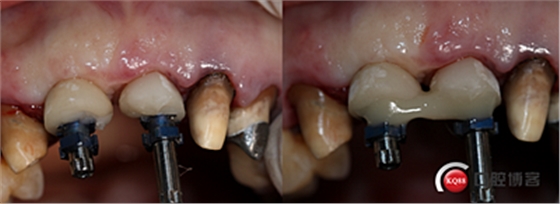

水平切口,鄰牙冠延長(zhǎng)。

擴(kuò)孔,檢查方向。

大家注意這個(gè)動(dòng)作,雖然不翻瓣,但要將唇側(cè)倒凹處骨膜剝離。

植入植體。

將骨粉塞入剝離的骨膜下間隙里既唇側(cè)倒凹處,盡量塞滿。

這時(shí)候縫合可能還會(huì)存在一些軟組織張力,這時(shí)候最好的辦法不是唇側(cè)減張縫合,看我的方法,既可以達(dá)到減張的目的又可以保證牙槽嵴頂角化齦充足。